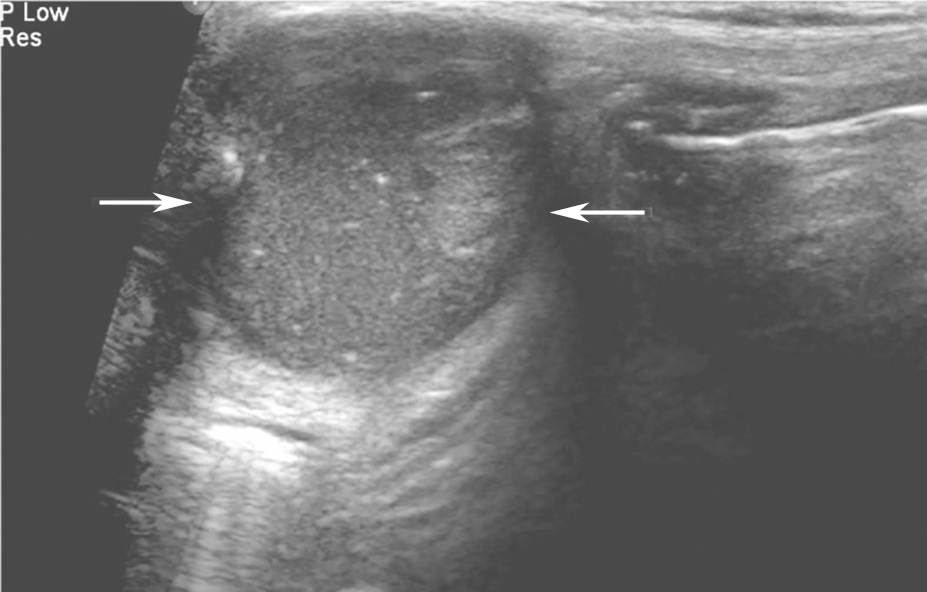

(十一)甲状腺髓样癌

甲状腺髓样癌超声上多为不规则低回声实性结节,内部回声不均,部分病例可伴有囊性成分,髓样癌丰富的血流信号是其超声主要特点。约1/3的髓样癌超声表现不典型,除了血供丰富表现外,类似良性结节(图13、图14)。

,分叶状,可见囊性成分及点状强回声(微小钙化).jpg)

图13左侧颈部纵切面:甲状腺左叶中部中低回声(箭头所示),分叶状,可见囊性成分及点状强回声(微小钙化)